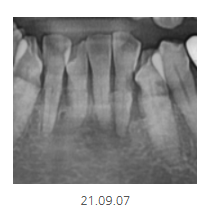

파노라마에서 1차 판별해 보니

의심되는 부분이 있다!!

그러면 추가 검사가 들어가게 됩니다.

이럴 때 선택적으로 작은 x-ray를 촬영합니다.

부분적으로 확대하여 촬영하기 때문에

더 자세히 볼 수 있습니다.